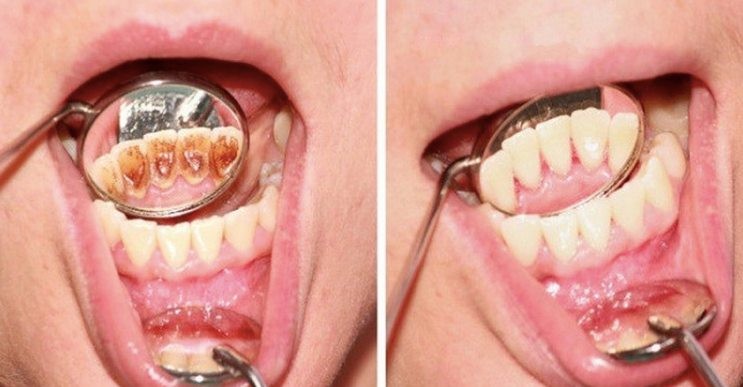

Dental plaque is a sticky, colorless cluster of bacteria that adheres to the teeth and along the edges of the gums. Over time it hardens and becomes tartar.

It is one of the main causes of tooth decay, gum inflammation, and other dental problems.

Fortunately, there is a simple but effective natural remedy that will help you get rid of tartar and plaque.

And what’s more, without having to visit your dentist and pay for expensive procedures, such as professional dental cleaning.